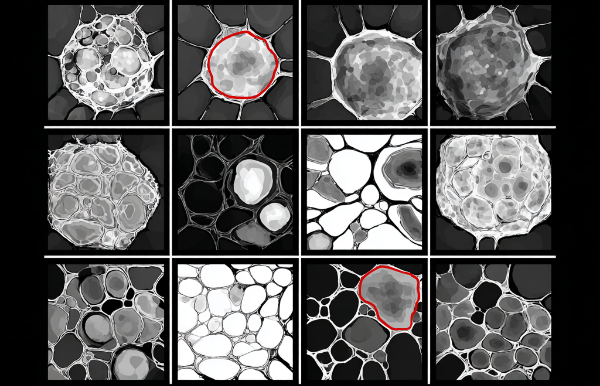

The figure below illustrates the semi-supervised learning workflow: the model is first trained on a small labeled dataset. It generates pseudo-labels for the unlabeled samples then retrains iteratively on both labeled and unlabeled datasets to improve performance.